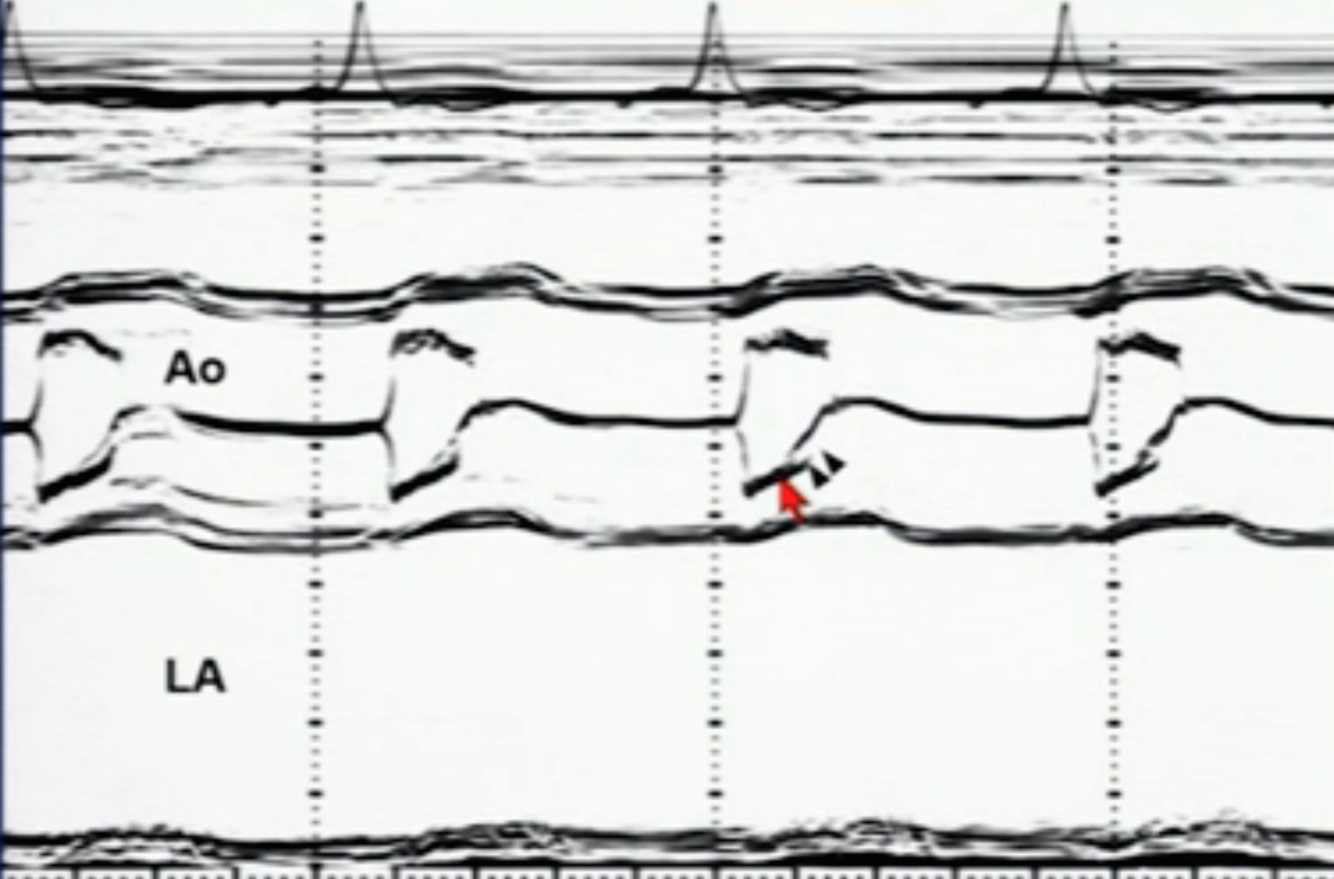

M-mode of AV w/ thickened leaflets and eccentric closure

Bicuspid AV

M-mode of AV with normal AV opening–> early systolic closure–> fluttering leaflets

Subaortic AS

M-mode of AV showing normal AV opening–> fluttering leaflet- -> mid-systolic closure

HCM/dynamic obstruction

M-mode of AV showing limited AV opening, thick leaflets, central/normal closure

Valvular AS